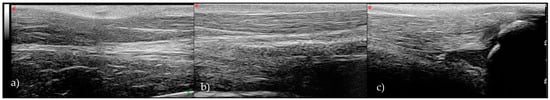

- Grade 1: Normal tendon with parallel fibers and homogeneous architecture

- Grade 2: Enlarged tendon with bowed margins and homogeneous architecture

- Grade 3: Hypoechoic area with or without tendon enlargement and bowed margins